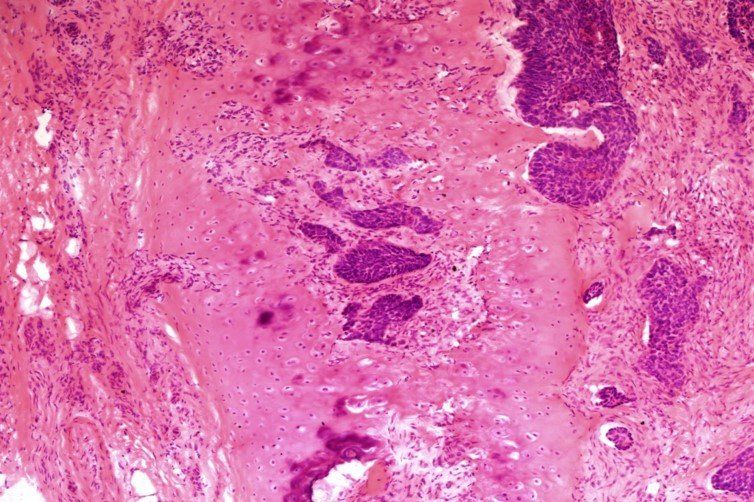

H E - BMT-ordning

Set ved x20. Alt i alt en meget god forberedelse, men der blev trukket point fra for folder og krøller, materialetab og baggrundsfarvning med hæmatoxylin. Dette præparat fik en score på 8/10.